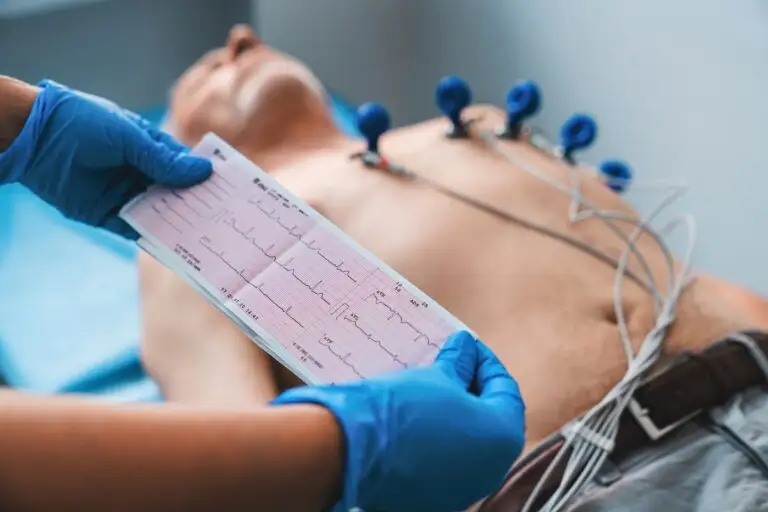

What Tests are Done to

Diagnose Bronchial Asthma?

Before doctors set a course of action for Bronchial Asthma treatment, they diagnose the condition to rule out certain conditions. The first stage in Bronchial Asthma diagnosis is for your doctor to analyze your personal and family medical history, discuss your types of allergies, and conduct a physical exam.

The following are the tests done for Bronchial Asthma diagnosis

- Spirometry - Spirometry is a kind of lung function test that gauges your lungs' general condition. It gauges how much air can flow effortlessly through your body and how much can enter and exit your lungs with each breath.

- Peak Expiratory Flow - Peak flow testing, which measures airflow using a handheld device, can help you manage your asthma every day by letting your doctor know how much space in your airways is constrained by inflammation.

- FeNO - With this test, you may find out how much nitric oxide is in your exhaled breath. Nitric oxide levels above normal can indicate lung inflammation. Breathing into a device that measures your nitric oxide levels is how this test is carried out.

- Chest X-ray - Chest X-rays can reveal other issues affecting your breathing, such as pneumonia or lung cancer, even though they are not helpful for diagnosing asthma.